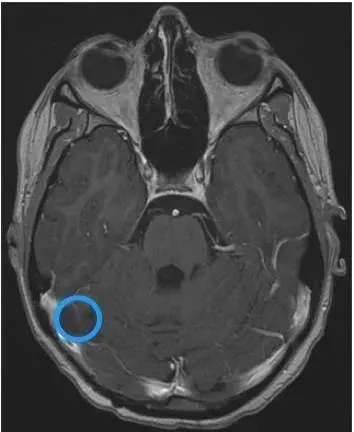

Cathy的手术很顺利,次全切的效果也很好:术后MRI显示Cathy的右侧横窦内小脑实质部分全部切除,有少量强化肿瘤(<1.5c㎡),残留的肿瘤侵犯了右侧横窦和乙状窦的交界处,被认为不适合安全切除,取而代之的是用双极烧灼法凝固该成分。

术后影像显示右侧横窦有一个小的残余肿瘤。C显示右侧横窦局灶性血流缺损。